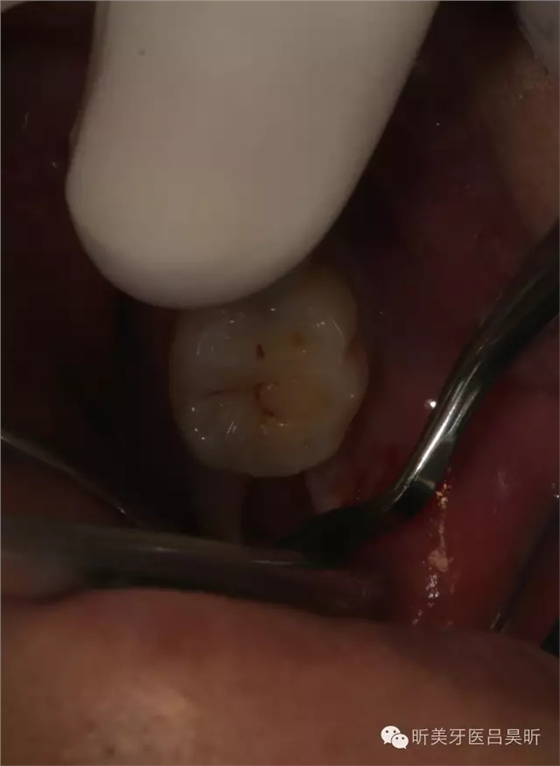

術(shù)前口內(nèi)掃描,設(shè)計冠修復(fù)方式和種植位點

可見種植位點舌側(cè)區(qū)凹陷,牙槽骨上部舌傾明顯。

擬定種植三維方向

以修復(fù)為導(dǎo)向的種植位點設(shè)計